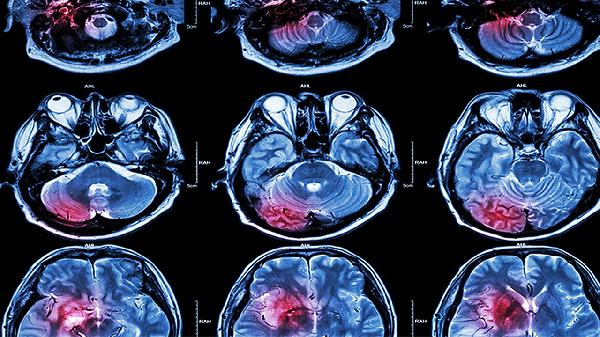

脑外伤后引发失忆症通常与脑组织损伤、神经传导中断等因素有关。失忆症的形成主要涉及海马体损伤、脑震荡、弥漫性轴索损伤、颅内血肿压迫、慢性创伤性脑病等机制。

海马体是大脑中负责记忆形成和存储的关键区域。脑外伤可能导致海马体直接受损或供血不足,影响短期记忆向长期记忆的转化过程。患者常表现为近期事件遗忘,但保留远期记忆。临床可通过头颅MRI检查明确损伤范围,治疗需结合神经营养药物如胞磷胆碱钠片、奥拉西坦胶囊等促进修复。